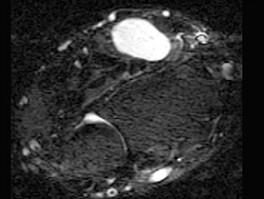

问题 男,69岁,腕部肿块1年,结合 图像,最可能的诊断是 ( )

选项 A、肌内脂肪瘤 B、未见异常 C、腕部腱鞘脓肿 D、腱鞘巨细胞瘤 E、腕部腱鞘囊肿

答案 E